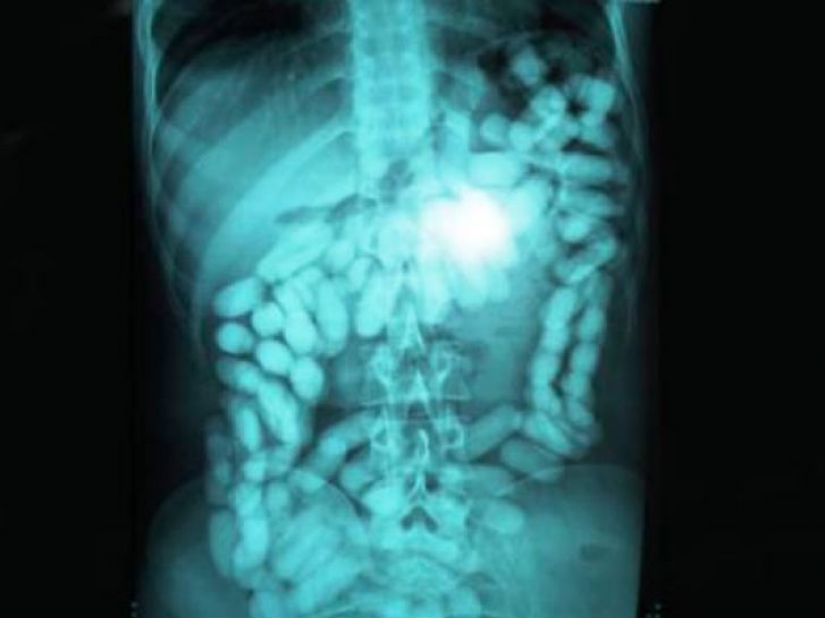

And it looks like the man who swallowed a considerable quantity of drugs to carry their contraband across the border.